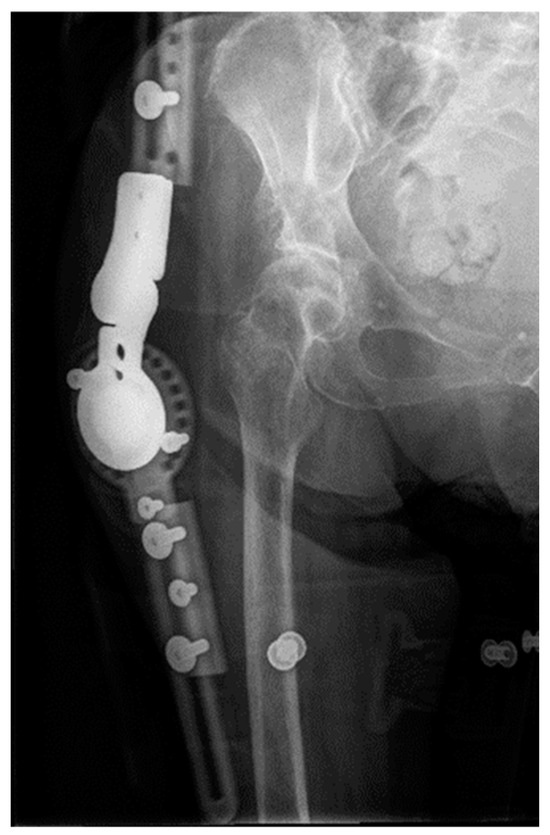

2.2. Complications after Treatment

2.3. Case Follow-Up